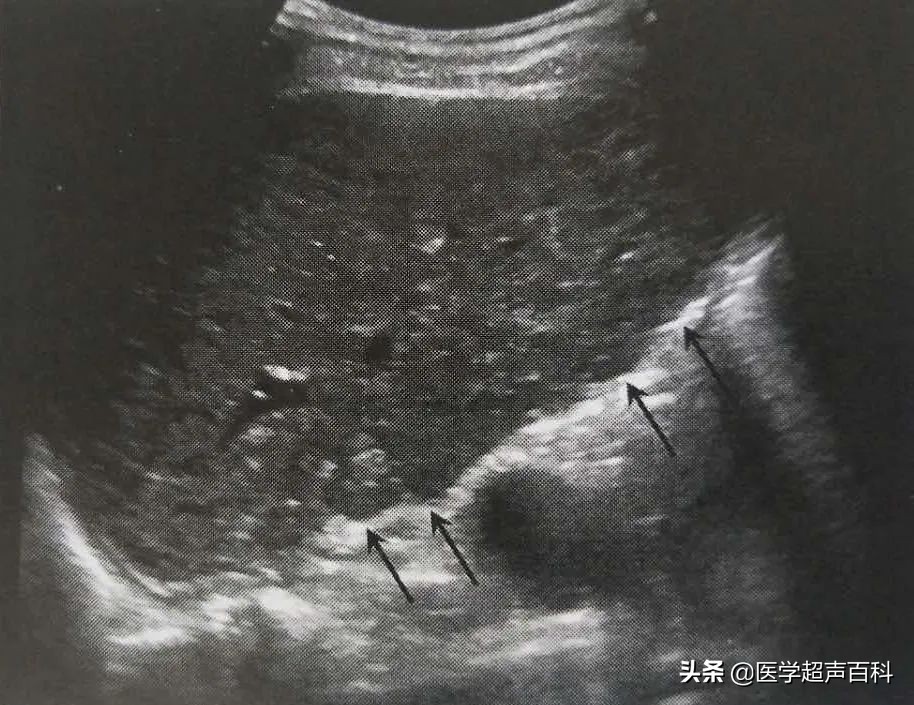

我一阵迷糊,还没反应过来,只听到一声“呕”,只见老大爷张嘴往外开始吐血(像水龙头的水一样往外涌),我一阵发蒙,这是什么情况?大概有4-5秒钟时间,等我反应过来,老大爷已经止吐。凭借经验,当时已经有所怀疑,顾不上再让他去交钱,问过他没再想吐的感觉,联系过医生后,赶紧把老大爷拉到床上,探头往上一放,果然--大量腹水,肝实质弥漫性回声改变, 肝包膜增厚,并且回声渐强,薄厚不均,肝的边缘角变钝、不规则 , 形态凹凸不平,显现结节状,并萎缩变形 ,门脉高压,脾大。